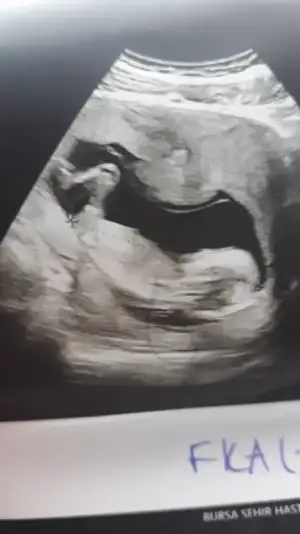

Erkek gibi sanki diyorumMerhaba doktor bi tahminde bulundu fakat siz ne düşünüyorsunuz merak ediyorum@Ikra meyra

Erkek görünüyorKızlar selamlar bebişime bakar mısınız rica etsem. Çok merak ediyorummdoktor kesin birşey söylemedi. Bir çıkıntı var dedi. 1 ay daha bekliycem. Buradan anlaşılır mı? 3. Fotoyu hiç anlamadım. Çok teşekkürler sevgiler

Evet doktorda erkek gibi görüyorum dediErkek gibi sanki diyorumönceki usglerde kız sanki demiştim

Buna göre erkek görünüyor ama en iyi 11 12 13 haftalar olmalıMerhabaIkra meyra , benim ultrason görüntülerime de bakabilir misiniz lütfen?

Teşekkür ederimBuna göre erkek görünüyor ama en iyi 11 12 13 haftalar olmalı